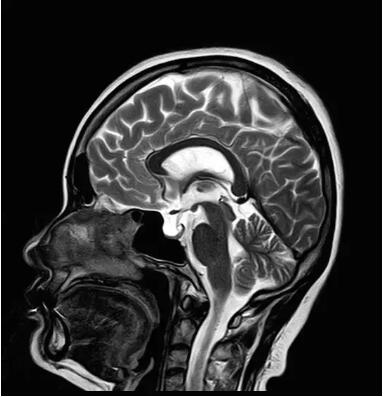

圖:搭載Pure射頻鏈全新一代1.5T磁共振

佳能磁共振推出了全新一代Vantage Elan1.5T磁共振,這款日本原裝進(jìn)口的 1.5T磁共振,集當(dāng)今磁共振創(chuàng)新科技成果于一身:

高精度鍍膜新磁體——鍍膜貼合技術(shù) 獲得最佳磁場均勻度

3DRSCE微雕梯度 ——精準(zhǔn)控制頻率和相位輸出理想波形

Pure  射頻影像鏈——圖像信噪比提升40%

“螢火蟲”成像技術(shù)——見所未見 微小腫瘤無處遁藏